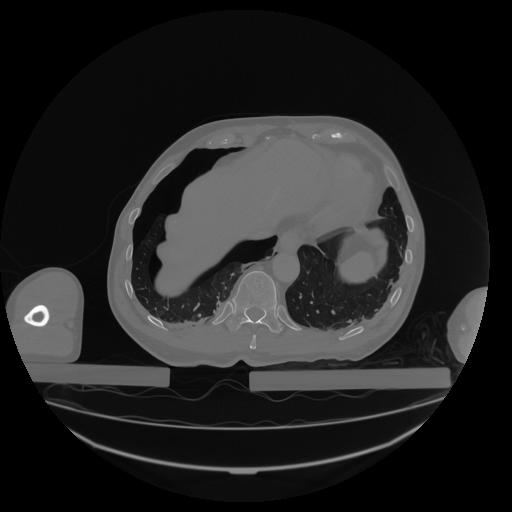

34 CUERPO,CE,Vol,1.0,CUERPO,,